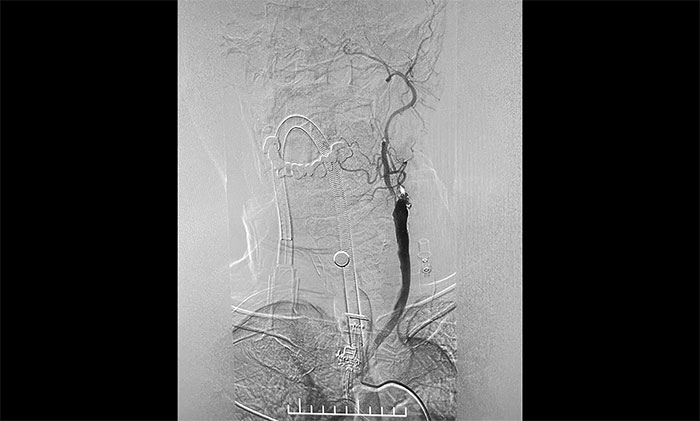

▲ DSA确诊左侧颈内动脉闭塞

脑血管造影显示,左颈总动脉起始段、下段中度狭窄,左颈外动脉起始段重度狭窄,左颈内动脉起始段闭塞,远端颈内动脉缓慢显影至眼动脉;左椎动脉、左大脑后动脉、基底动脉显影,左椎V4段经侧枝向左侧枕动脉代偿供血至左颈外动脉;右颈内动脉起始段轻度狭窄。